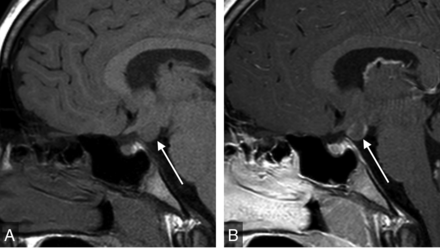

Sagittal T1WI of the sella (A) demonstrates a gray matter–isointense suprasellar mass lesion (arrow). Sagittal postgadolinium T1WI (B) shows enhancement, indicating a diagnosis of neoplasm (hypothalamic glioma) rather than hamartoma.

The remaining 9 of 40 discrepancies (23%) required contrast for definitive characterization. Six were extrasellar masses, which included 2 suprasellar arachnoid cysts, 2 hypothalamic hamartomas, 1 hypothalamic glioma, and 1 case of an atypical mass along the pituitary stalk. The 3 cases of stalk abnormalities that required contrast for complete characterization were a case of duplicated stalk and 2 cases of a thickened, enhancing pituitary stalk. Figure 2 summarizes the discrepant findings.